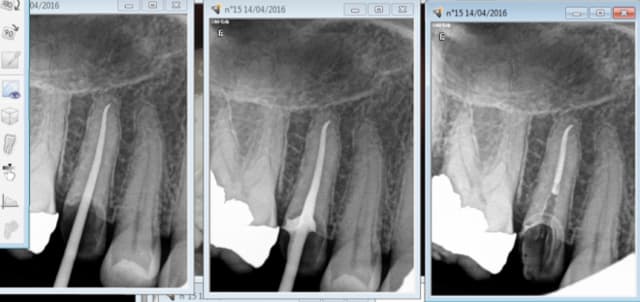

14/04/2016 à 17h25

vu le tarif de merde des endos tu peux aussi t'arreter au cone scellé. -)

Ca donne de très belles images. tout comme l'essayage du cone d'ailleurs, on a pas forcément mieux condensé. -)-)

Capture d e cran 2016 04 14 15.23 - Eugenol

Capture d e cran 2016 04 14 15.25 - Eugenol